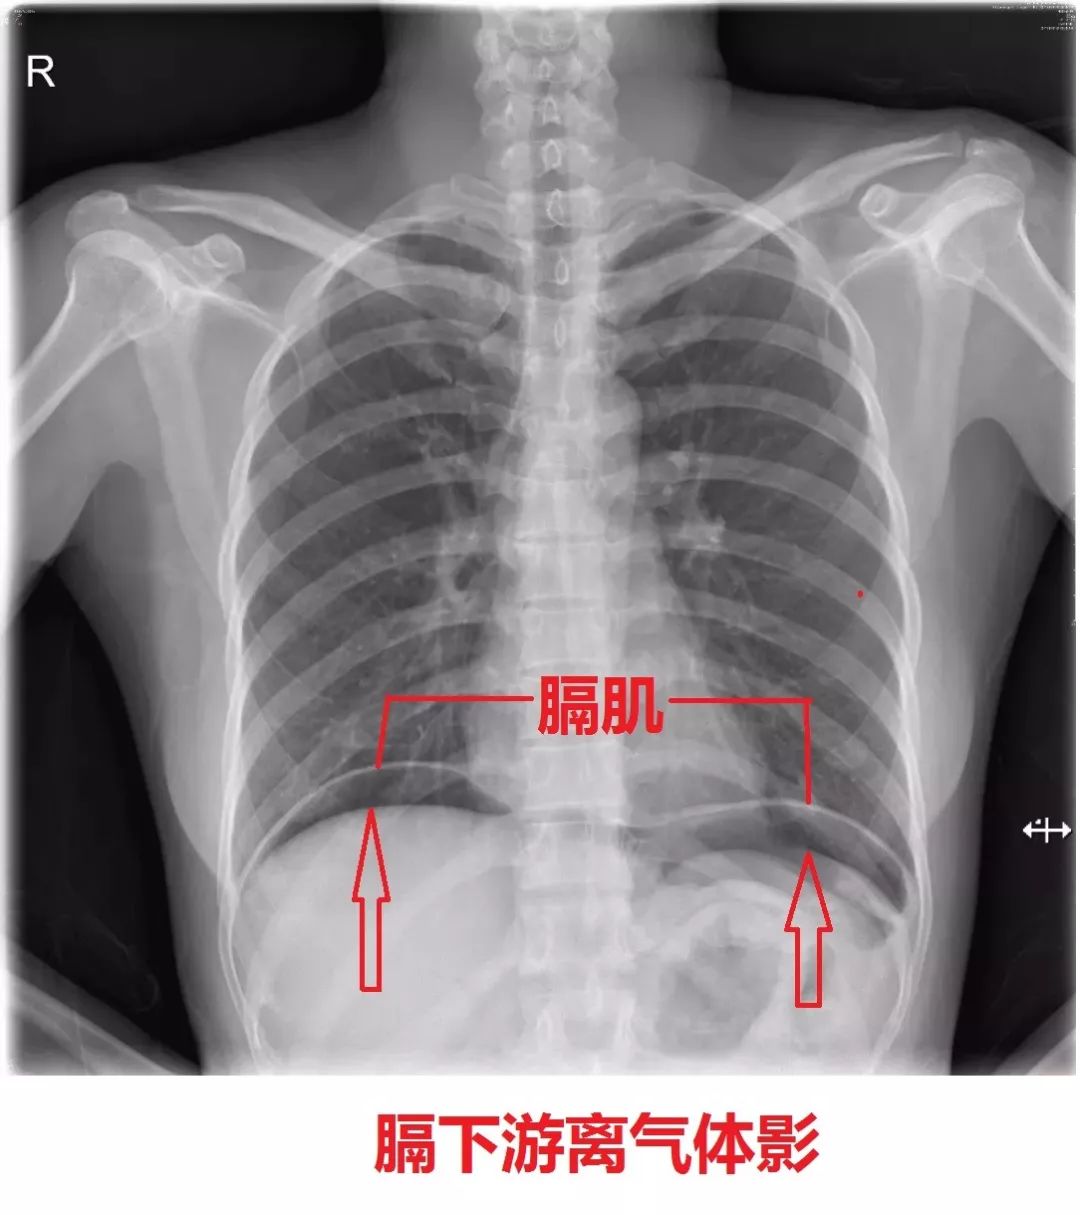

大家可能不知道膈下游离气体影意味着什么,我来简单解释一下。正常人的胸腔、腹腔是分隔开的,就是通过膈肌来隔开,膈肌以上是胸腔,膈肌以下是腹腔。腹腔里面有很多脏器,包括胃、十二指肠、回肠、空肠、结肠,还有肝脏、胆囊、脾脏、肾脏、胰腺、系膜网膜等等,整个肚子是被塞得满满的,一般情况下,腹腔是没有气体的,但是胃、肠道里面会有气体,但胃肠道跟腹腔不通,所以胃肠道的气体不会进入腹腔。但如果胃肠道有穿孔破裂,那么里面的气体就会进入腹腔,这时候腹腔也会有气体了,当然肠道里面的液体、细菌也会进入腹腔。

胃肠道气体进入腹腔后,气体会积聚在膈肌下面,因为当人站立位时,膈肌下方是最高的,气体自然往高处走,所以会出现膈下气体,而且这些气体是游动、游离的。

这边是膈下游离气体,通常意味着胃肠道穿孔了!

外科医生摸肚子无数,看急腹症病人无数,对膈下游离气体还是很有信心的,而且他亲自看了片子了,的确是右侧膈肌下有气体影。

那个所谓的膈下游离气体影,原来是一侧结肠在搞的鬼!

正常情况下,膈肌下就是肝脏和胃,肝脏下面才是结肠,也就是说膈下方和结肠是相距一段距离的,但这个方女士的结肠有一段位置跑偏了,这段结肠没有乖乖地按照本来的轨道走,而是绕过肝脏往上,直奔膈肌下方了。刚好这段结肠没有大便填充,是空荡荡的,里面都是气体,而这段结肠又正好处于右侧膈下.....所以影像科医生就以为是膈下游离气体,以为是胃肠道穿孔导致的。

不单只影像科医生这么认为,外科医生也是这么考虑的。这事不能全怪人家。

方女士这段走向异常的结肠(结肠异位)差点送她上了手术台。

日常生活中,结肠异位并不罕见,因为结肠很长,有1-2米长,在腹腔内绕了个大圈,像个“口”字一样,这就不难理解为什么会有些人的某一段结肠位置跑偏了。一般情况下结肠位置移动了一下不至于出大问题,但像方女士这样的情况,就容易搞乌龙了。